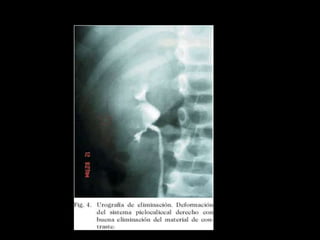

Diagnostico

Estudios de imagen

• Urografía excretora

• TAC

• Pielografía anterógrada o retrógrada

Diagnostico • Sospecharla: mecanismolesión, fiebre, • leucocitosis, irritación local peritoneal • Hematuria • Reconocimiento intraoperatorio Estudios de imagen • Urografía excretora • TAC • Pielografía anterógrada o retrógrada